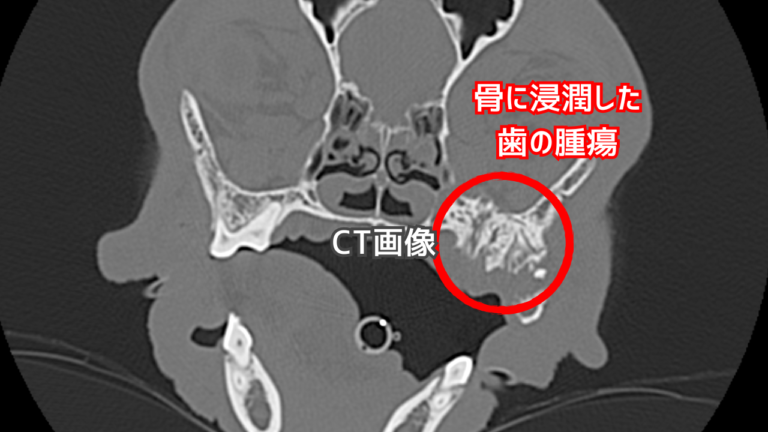

露髄が起こってしまうと、細菌が歯の内部に侵入し、細菌感染が起き、歯髄は壊死し、症状が進むと根の先の炎症「根尖性歯周炎」が起きてします。

・根尖周囲病巣の有無